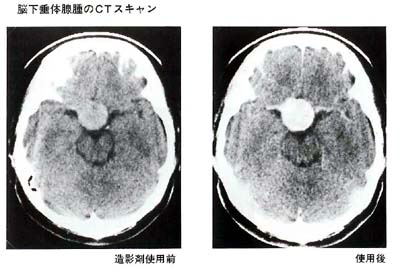

(2)CTスキャン

(1)は脳下垂体を包んでいる骨の変化を調べるもので、いわば腺腫の間接的な診断にすぎません。

一方、CTスキャンは腺腫自体を描出出来ますので、その正確な大きさと拡がりを知ることが可能です。造影剤を点滴する前と後とで2回検査を行ない、その差を調べます。この際、まれに造影剤によってじんましん等アレルギー症状を示す方がいます。